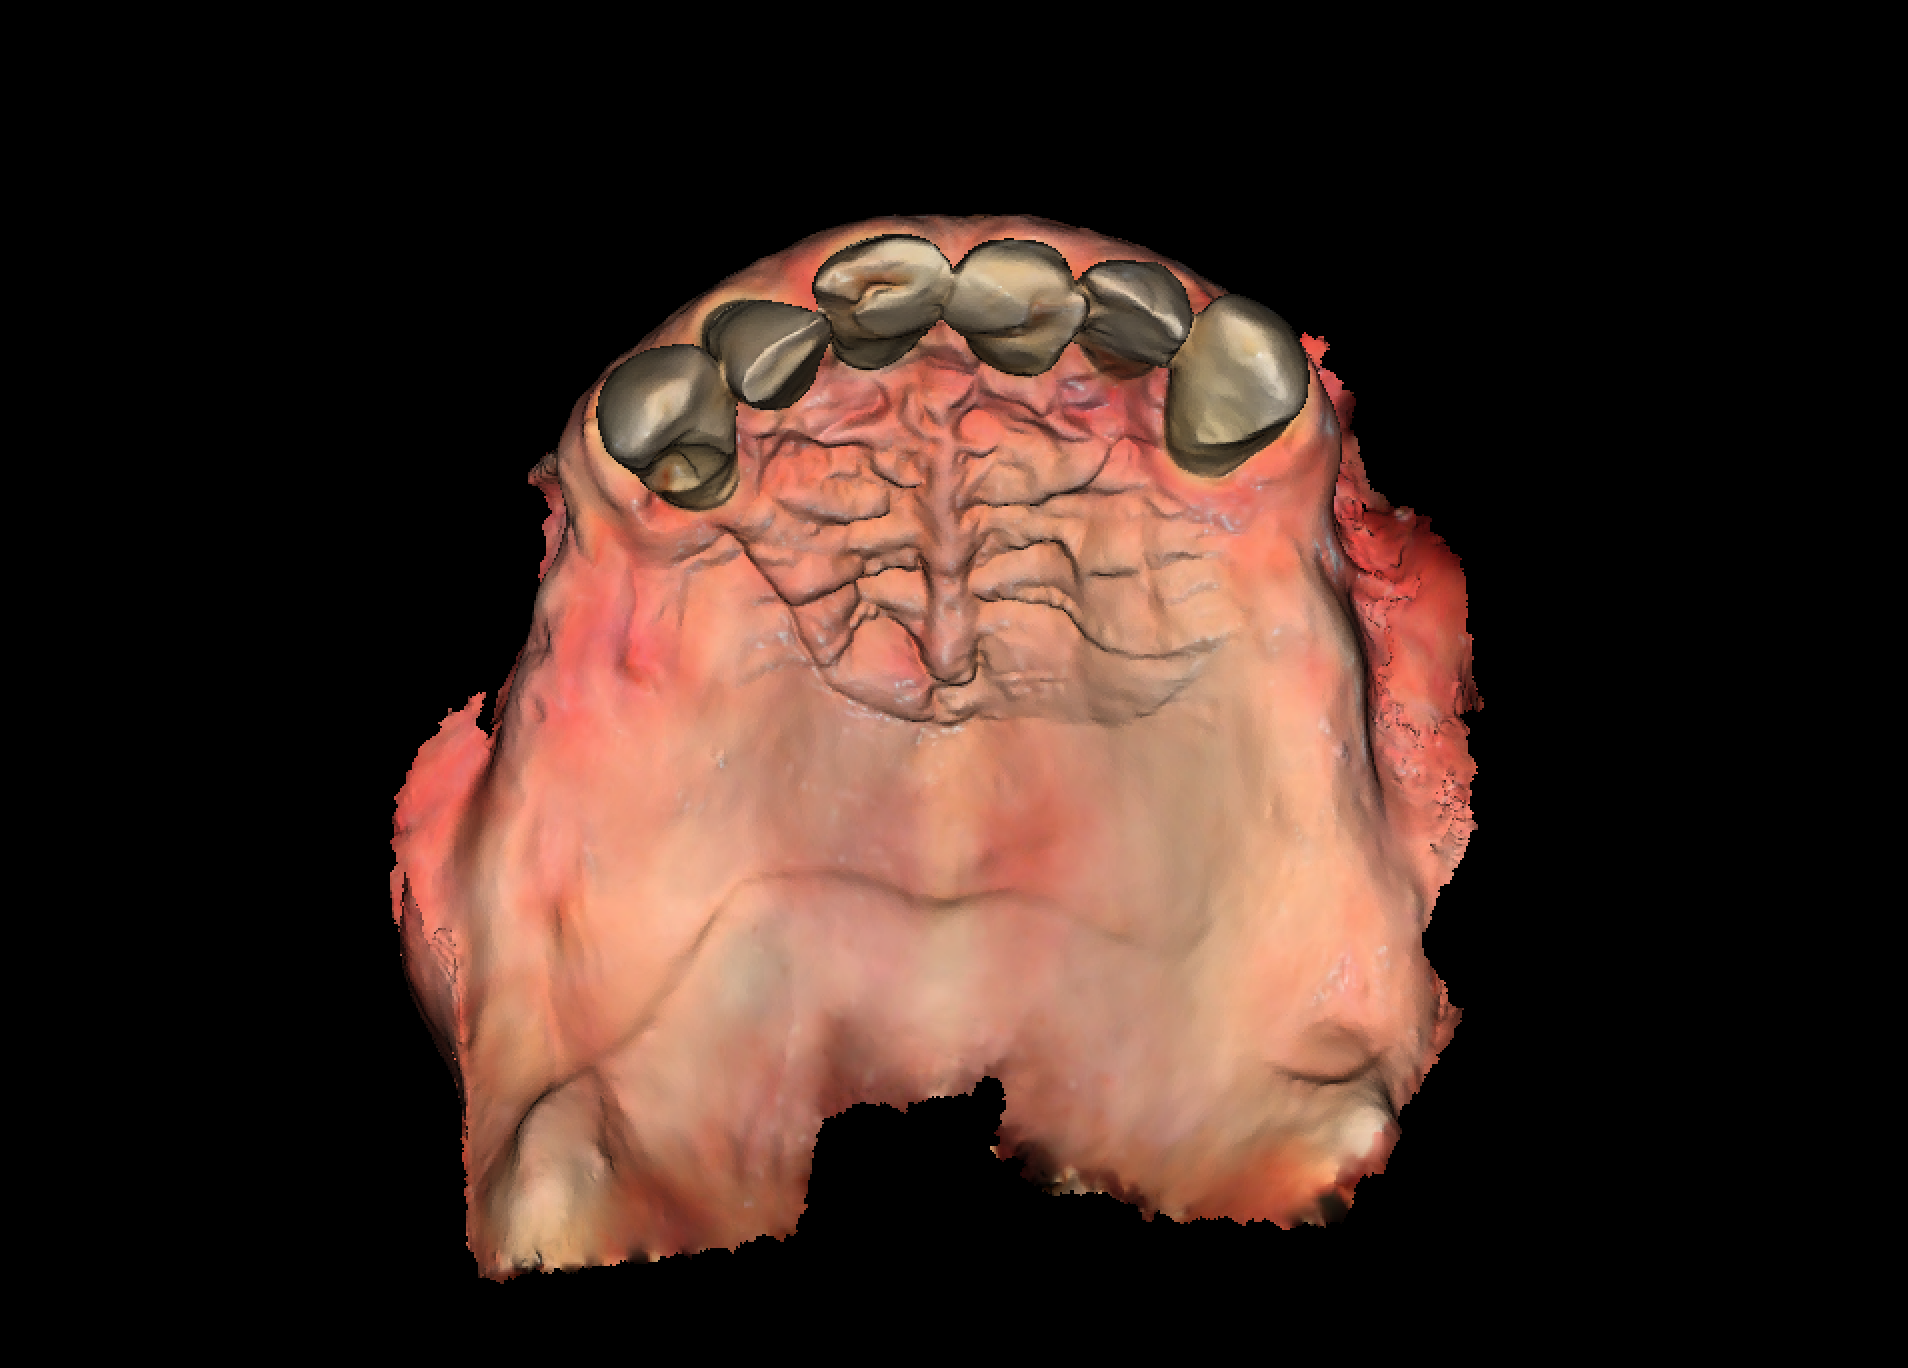

Initial diagnostics included CBCT imaging and full-arch intraoral scanning. A digital wax-up with an increased vertical dimension of approximately 2 mm was created to simulate functional and aesthetic improvements. Fully digital implant planning was carried out, and a SMOP tooth supported guide was designed, anchored in the region of the lateral incisors.

Following the extraction of teeth 13–23, the tooth-supported guide was positioned and stabilized, allowing precise, fully guided implant surgery. Multi-Unit Abutments were inserted according to the digital plan. Immediately post-surgery, intraoral photogrammetry was performed to record the implant positions with high accuracy, eliminating the need for conventional impressions or splinting.

Healing progressed without complications. Stable peri-implant soft tissues and successful osseointegration were observed. After removal of the provisional restoration, a second intraoral photogrammetry scan was performed to document the implant positions at the time of prosthetic release. These data were transferred to the patient’s general dentist for final restoration fabrication.